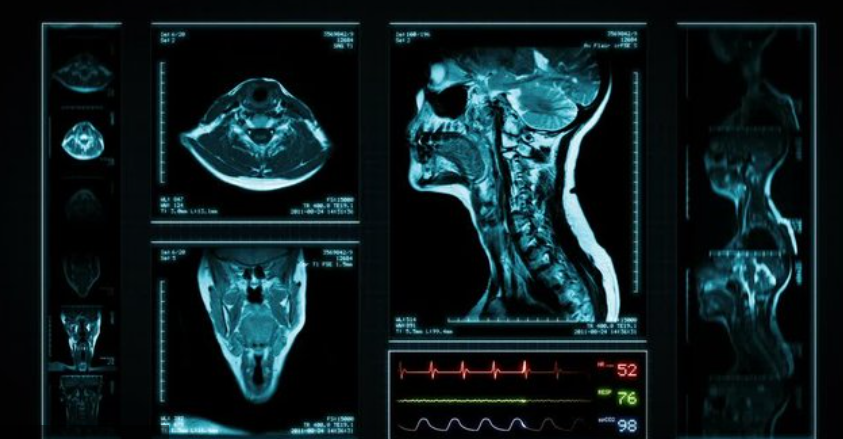

Magnetic Resonance Imaging (MRI) has become a cornerstone of modern healthcare, not only for its diagnostic precision but also for its ability to shape value-based medical treatment. Traditional healthcare models often prioritize volume—more procedures and scans—rather than measurable patient outcomes. MRI, with its ability to provide high-resolution, actionable insights, is redefining the approach to clinical decision-making and resource allocation.

As hospitals and health systems shift toward value-based care, MRI is proving to be an indispensable tool for improving outcomes, reducing unnecessary interventions, and enhancing overall healthcare efficiency.